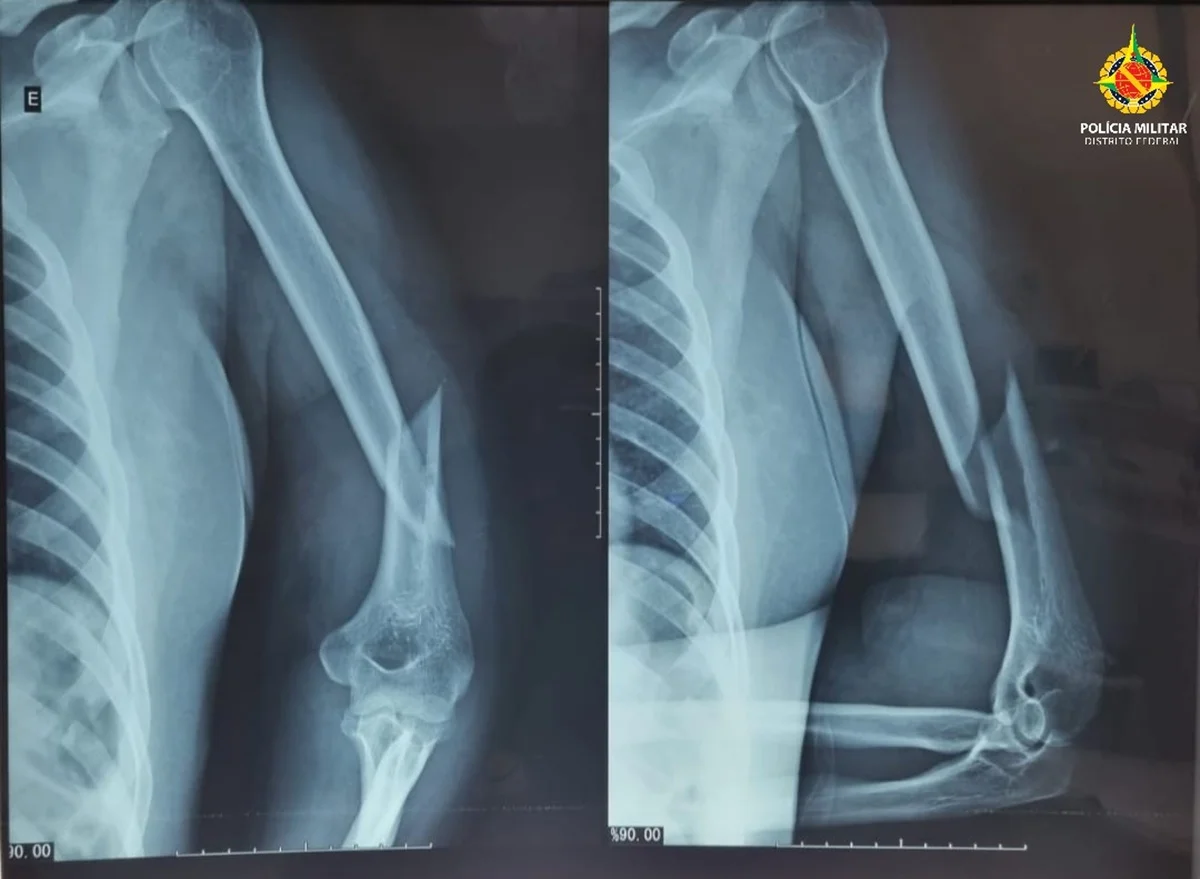

Segundo a Polícia Militar do Distrito Federal (PMDF), uma equipe foi acionada para atender um caso de violência doméstica, e ao chegar ao local constatou que a vítima apresentava vários ferimentos, incluindo hematomas no rosto, inchaço ao redor dos olhos, sangramento nos ouvidos, além de fratura no úmero esquerdo e luxação no ombro esquerdo.